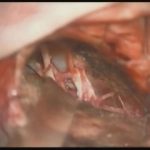

術中写真

摘出 前